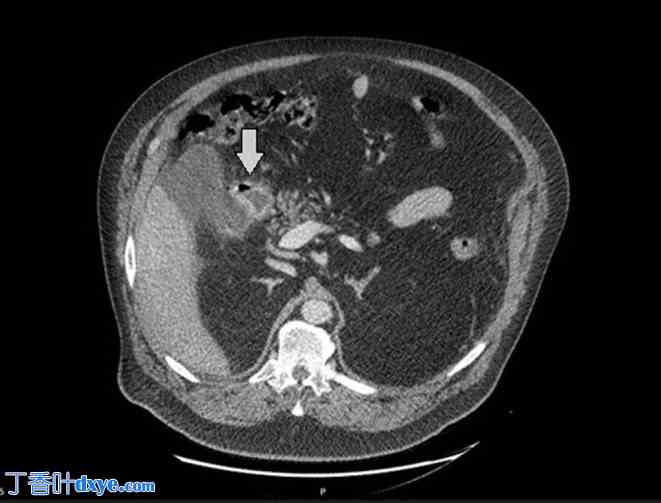

持续性疼痛导致腹部计算机断层扫描 (CT) 显示腹腔内游离液体、十二指肠壁增厚和游离气体(图 1 和图 2)。怀疑十二指肠穿孔。

图 2.

CT 显示腹腔内游离液体。